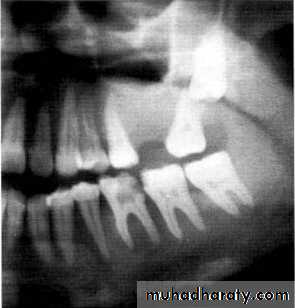

A 11-year-old female with swelling on the right side.

impacted canine

Ameloblasoma*Non-metastasizing tumor originating from remnants of the odontogenic epithelium of the enamel organ or dental lamina. *Associated with the crown of impacted teeth.

*80% located in the bicuspid & molar regions.

*Shape: is either unicystic or soap bubble-like lesion, Expansile, *Tooth migration is common,teeth in the area are vital.

*Adjacent teeth displaced, loosened , often resorbed

Extensive expansion in all dimensions

Maxillary lesions can extend into the paranasal sinuses, orbit or base of the skull.

Male > female.

Age; > 30 years